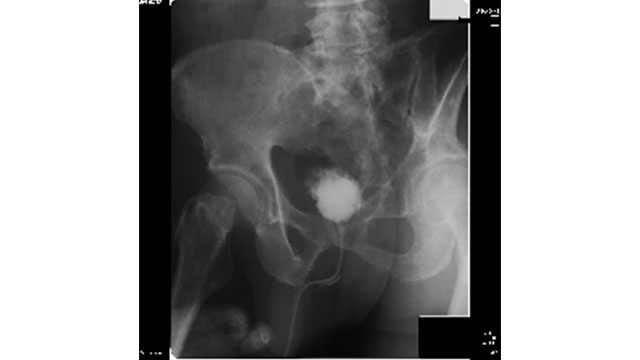

胸部、腹部、整形等の検査をX線を用いて行います。泌尿器領域ではKUBという腎臓、尿管、膀胱を目的とした撮影を行い、結石などの診断に用います。

体の外で衝撃波を発生、その衝撃波を結石に集中させる事で結石のみを破砕します。 治療装置のヘッドと呼ばれる部分を体に密着させることで治療を行います、手術のような外科的処置は行わないので日帰り治療が可能です。

治療時間は準備を含めて1時間ほど、3000発前後の衝撃波を当てます。 治療中は衝撃波の発生によってカンカンカンと音が聞こえます。 写真の水の入った風船のような所を体に密着させて治療を行います。